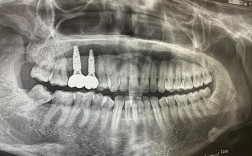

“种一颗牙到底要花多少钱?”这是许多缺牙患者咨询时最关心的问题,作为从业15年的牙科专家,我深知种植牙不仅是“修复缺牙”,更是对生活质量的长期投资,我们就来全面拆解种植牙的费用构成,告诉你为什么有人花3000元就能种,有人却要花2万+,以及如何根据自己的情况选择性价比最高的方案。

目前国内单颗种植牙的总费用(从检查到戴牙完成),主流区间在5000元-30000元不等,这个差异主要源于种植体品牌、牙冠材料、医生技术、患者自身条件、医院资质五大因素。